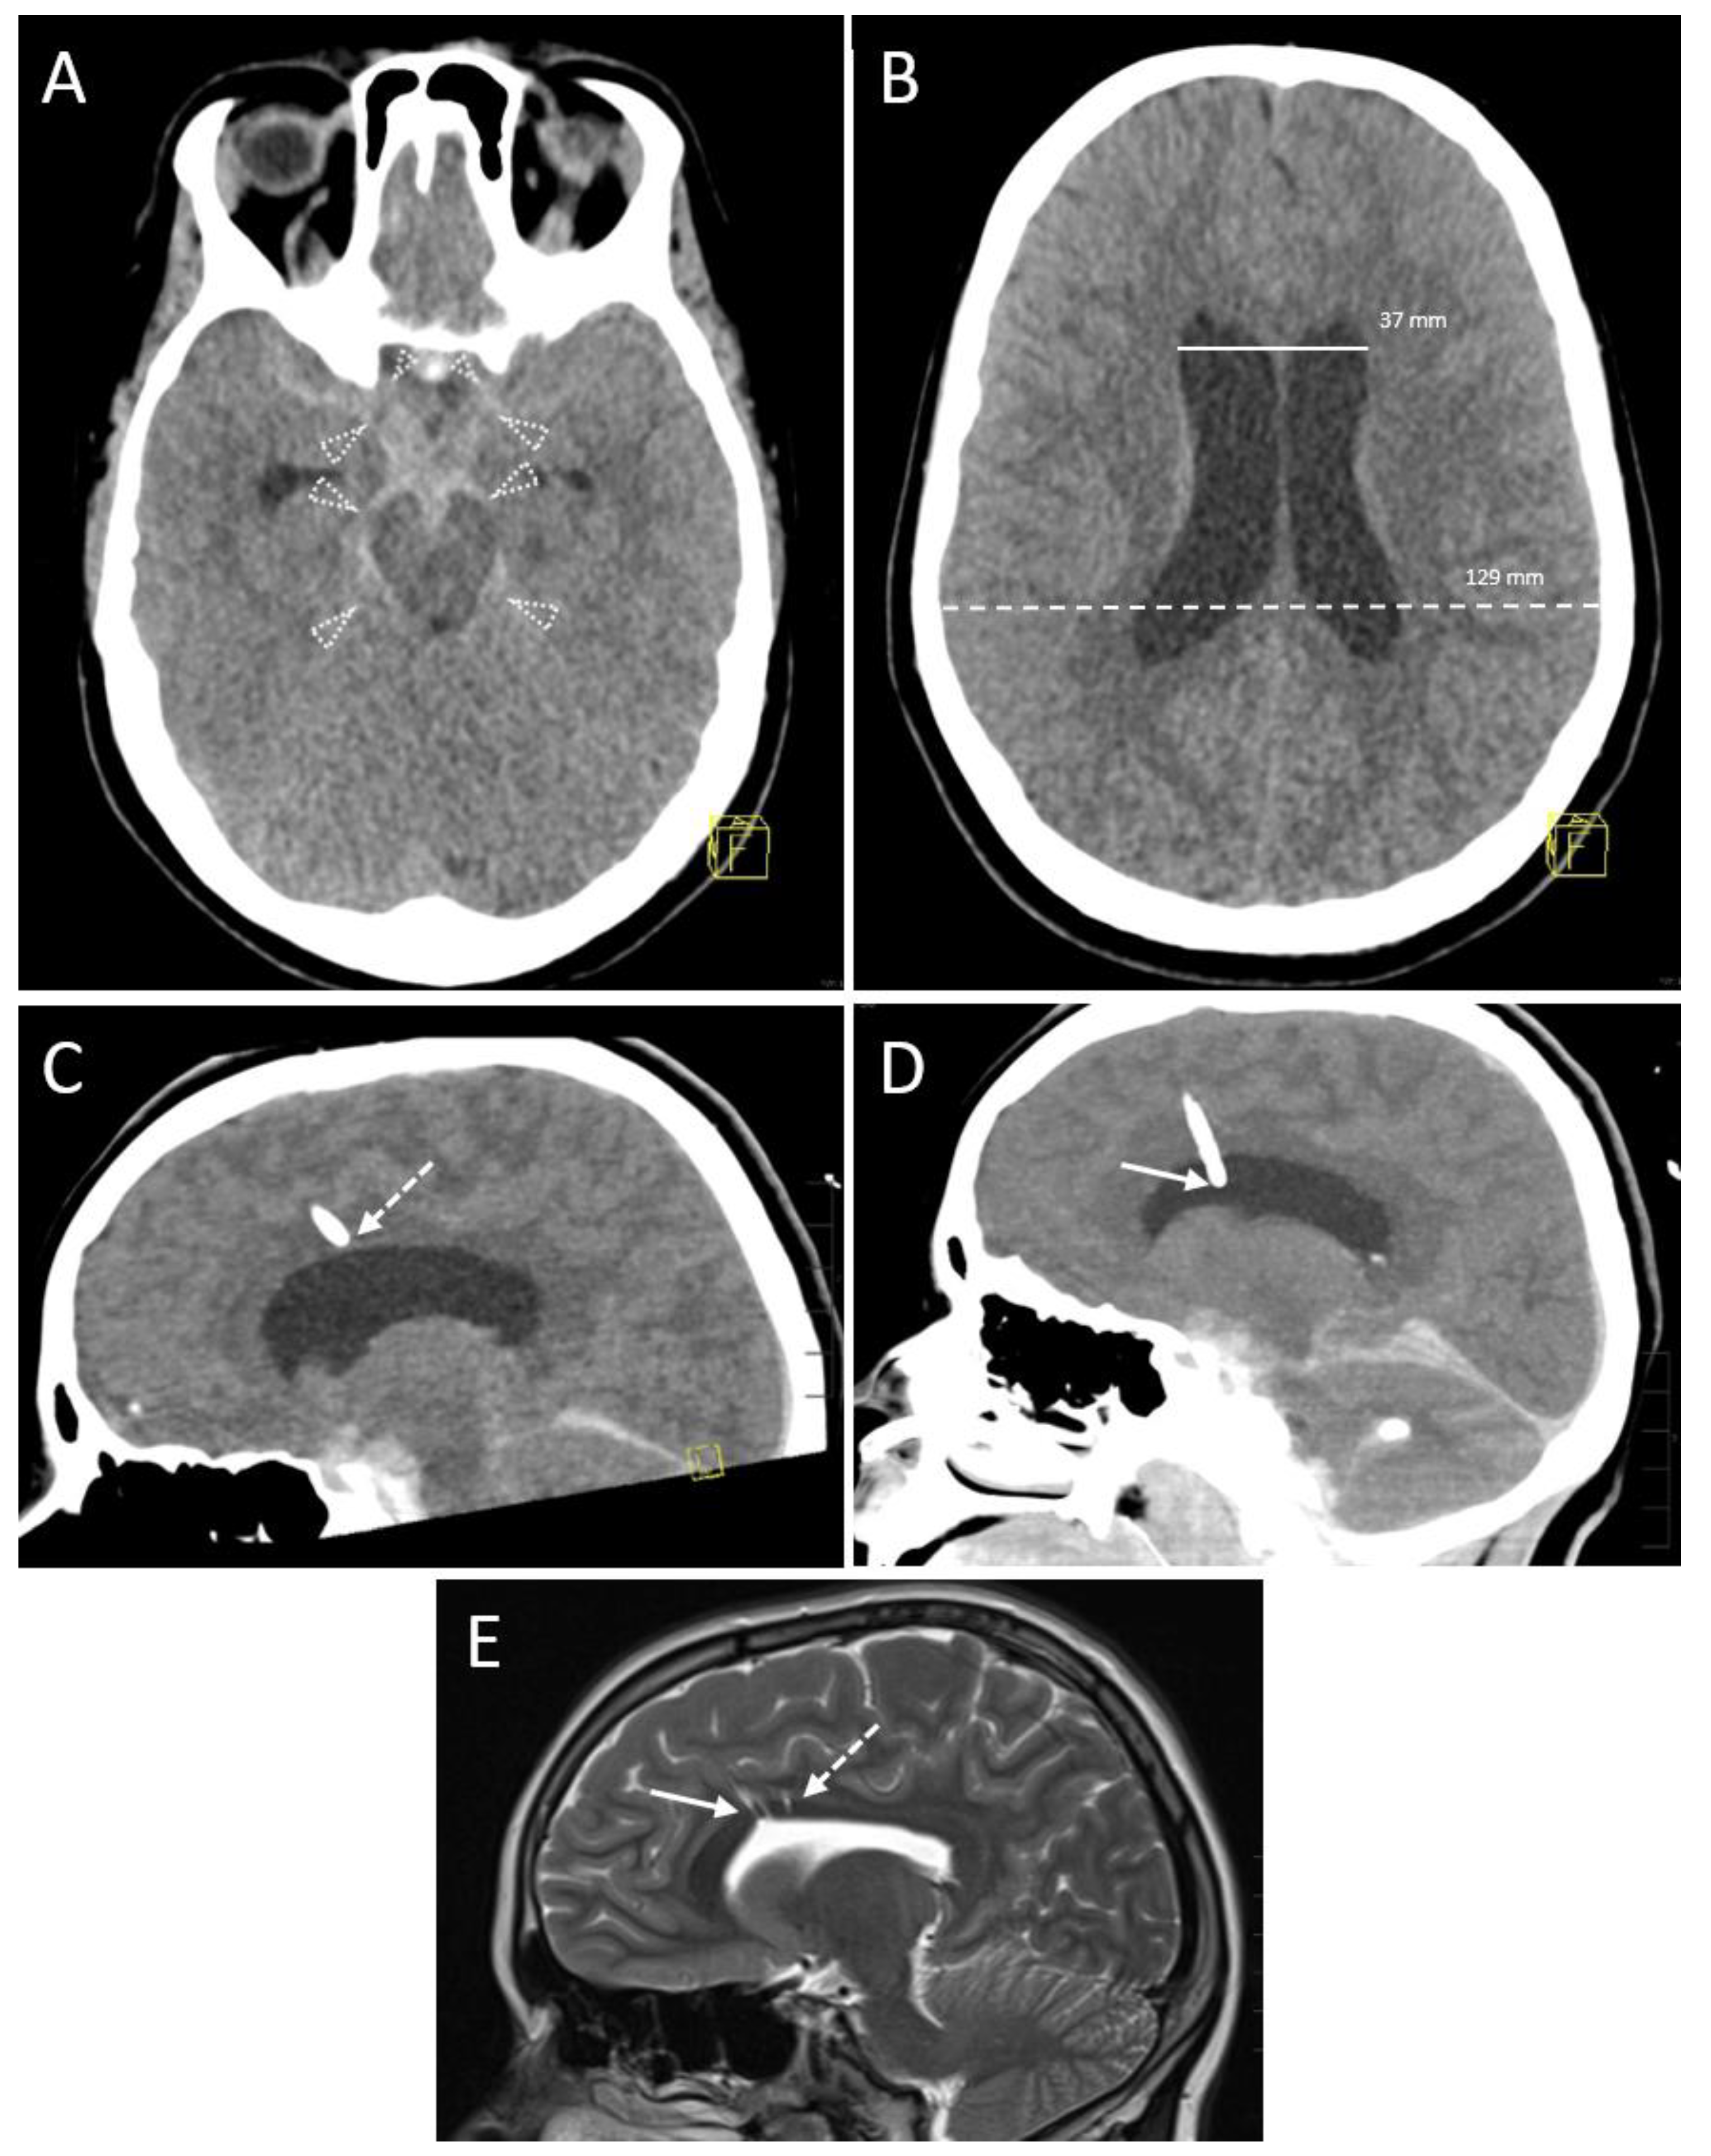

3.2.4. Hemorrhage

According to the classification by Wiesmann and Mayer [20], after 32 (88.9%) interventions, there was no evidence of hemorrhage in the immediate control CT scan and remaining follow-up CT scans acquired during the first 7 days after EVD placement (Table 3). Conversely, Grade 1 and 2 (Figure 4) hemorrhages were seen after 3 (8.3%) and 1 (2.8%) session(s), respectively. Grade 3 bleedings did not occur (0.0%).

Figure 4.

A 16-year-old boy after a motorbike accident. Axial (A) and coronal reformation (B) of the CT scan acquired immediately after the trauma revealed traumatic subdural hematoma (solid arrowheads), midline shift to the right (transparent arrowheads), uncal herniation (asterisk) and traumatic subarachnoid bleeding because of blood collection in the posterior horn of the left ventricle (arrow). A left-sided decompressive trepanation was conducted. Yellow graphic: orientation cube (a: anterior, f: frontal). (C) After one month, a posttraumatic hydrocephalus developed with increasing width of the ventricles. Thus, the indication for an EVD placement was made. Note the infarction of the posterior cerebral artery territory which had occurred due to the herniation and which is now clearly demarcated (asterisk). The left hemispheric brain exceeds the trepanation margins. Onset of general brain atrophy could also be seen. Yellow graphic: orientation cube (f: frontal). (D) Coronal Maximum Intensity Projection (MIP; 4 mm slice thickness) of the control scan after EVD placement shows the tip in the frontal horn of the right ventricle (Kakarla I). Yellow graphic: orientation cube (a: anterior). (E) However, after 3 days the EVD has been removed due to clotting (dotted arrow) and intraparenchymal hemorrhage (dashed arrow; volume ≥ 1 to 15 mL, Grade 2 according to Wiesmann and Mayer). Yellow graphic: orientation cube (a: anterior). (F) Coronal Maximum Intensity Projection (MIP; 20 mm slice thickness) of the control scan after placement of the new EVD. Its tip (solid arrow) is located near the septum pellucidum (Kakarla I). Clotting (dotted arrow) and intraparenchymal hemorrhage (dashed arrow) caused by the former EVD are still visible. Yellow graphic: orientation cube (a: anterior).